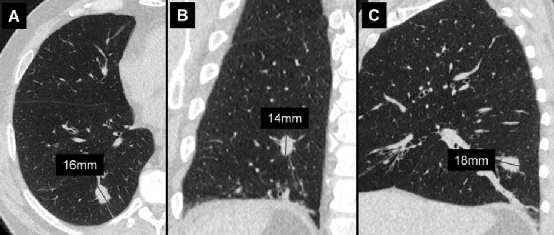

图A、左肺下叶实性结节。图B、最大长轴直径 (16mm,垂直箭头),垂直于长轴测量的最大短轴直径 (14mm,水平箭头)。结节的平均直径为15mm。

如肺小结节 (<10mm) 的尺寸应表示为同一平面内最大长轴和垂直最大短轴测量值的平均值。对于较大的结节或肿块 (>10mm),应记录长轴和短轴直径。因为该结节的平均直径>10mm,所以给出了长轴和短轴直径。

左肺上叶纯磨玻璃结节。前一病例的结节测量方法同样适用于此病例,此结节的平均直径为17mm。